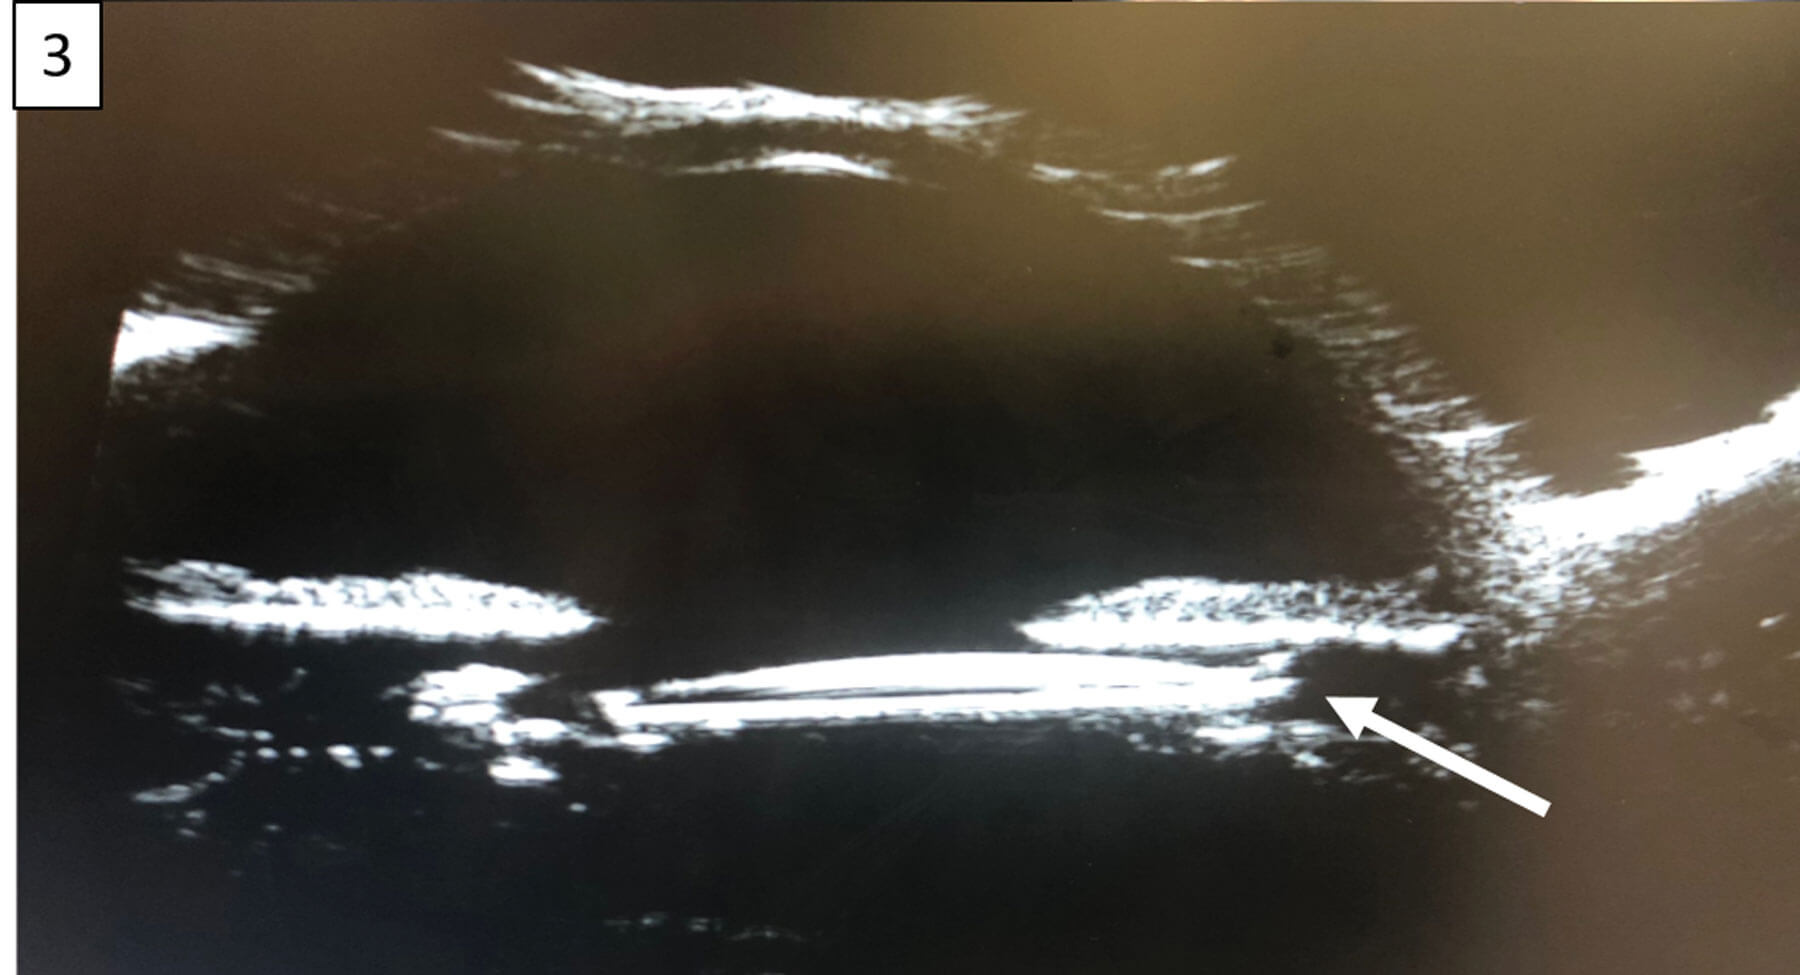

Figure 3: Ultrasound biomicroscopy demonstrated IOL decentration

and displacement of the superior haptic into the ciliary sulcus.

At one-month follow-up, the IOL was superiorly displaced with a haptic-like transillumination defect of the nasal iris (Figure 1). Gonioscopy of the left eye revealed dense pigmentation of the angle structures (Figure 2). Ultrasound biomicroscopy demonstrated IOL decentration and displacement of the superior haptic into the ciliary sulcus (Figure 3), resulting in persistent mechanical chafing of the posterior iris. Intraocular pressure was elevated to the mid-20s due to secondary pigment dispersion. The patient was taken to the operating room for lens explantation and secondary anterior chamber IOL placement.